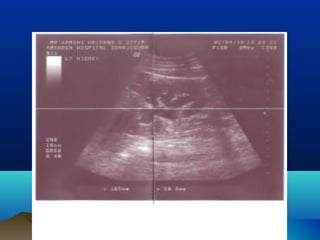

โ€ข ULTRASONOGRAPHY

โ€ข HYDRONEPHROSIS

โ€ข PARENCHYMAL THICKNESS